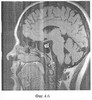

На фиг.4.1-7 показаны результирующие семь изображений, проходящие в сагиттальной плоскости через гипофиз. При этом фиг.4.1 проходит в непосредственной близости от турецкого седла справа, через сифон внутренней сонной артерии, гипофиз не затрагивает;

фиг.4.2 проходит через край турецкого седла и также не затрагивает гипофиз, а поэтому площадь сечения не обводится;

фиг.4.3 – область гипофиза в сагиттальном сечении обведена белой пунктирной линией; видно, что форма гипофиза в сагиттальном сечении сложная. Обведенная площадь сечения равна 0,42 см2;

фиг.4.4 – область гипофиза с приподнятой задней долькой, обведена пунктиром, его площадь в сагиттальном сечении равна 0,5 см2;

фиг.4.5 – сагиттальный срез на уровне воронки гипофиза. Площадь обведенного сечения равна 0,51 см2;

фиг.4.6 – краевой сагиттальный срез через гипофиз слева, площадь, обведенная по гипофизу, равна 0,3 см2.

На фиг.4.7 видно, что срез уже проходит значительно левее турецкого седла, через сифон внутренней сонной артерии, за пределами гипофиза и, следовательно, он не обводится.